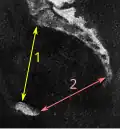

Размеры таза

Размеры и форма таза имеют важное значение для родового процесса и подлежат измерению и оценке у всех беременных. Для определения внешних размеров таза у живого человека пользуются измерительным инструментом — тазомером Мартина, внутренние размеры выясняются расчётными методами исходя из внешних, также применяется мануальное исследование через влагалище и ультразвуковые исследования. Рентгенологические исследования, в том числе компьютерная томография, у беременных применяются в исключительных случаях для уточнения в виду нежелательного влияния ионизирующего излучения на плод и красный костный мозг женщины[1].

Размеры таза (в скобках у мужчин)[2]:

- Distantia interspinosa — между верхними передними подвздошными остями — 23-25 (21-23) см

- Conjugata anatomica или diameter recta (анатомическая конъюгата/прямой диаметр верхней апертуры) — между мысом крестца и верхним краем лобкового симфиза — 11,5 (10,8) см

- Diameter transversa (поперечный диаметр верхней апертуры) — наиболее отдалённое между пограничными линиями — 13,5 (12,8) см

- Diameter obliqua (косой диаметр) — между расположенными с противоположных сторон крестцово-подвздошным суставом и подвздошно-лобковым возвышением — 12,0-12,6 (12,0-12,2) см

- Прямой размер таза — между стыком II и III крестцовых позвонков и задней частью середины лобкового симфиза — 12,2 (10,8) см

- Поперечный размер таза — между центрами вертлюжных впадин — 11,5 (10,8)

- Прямой диаметр нижней апертуры — между вершиной копчика и нижним краем лобкового симфиза — 9,5 (7,5)

- Поперечный диаметр нижней апертуры — между седалищными буграми — 10,8 (8,1) см

- Угол наклона таза - угол между горизонтальной плоскостью и плоскостью верхней апертуры таза

Акушерские размеры женского таза

В гинекологии и акушерстве, кроме упомянутых, имеют значение ещё следующие размеры таза[2]:

- Distantia intercristalis — между подвздошными гребнями тазовых костей — 25-27 см

- Distantia intertrochanterica — между большими вертелами бедренных костей — 28-29 см

- Conjugata vera (истинная гинекологическая конъюгата) — между мысом крестца и самой задней точкой лобкового симфиза — 10,5-11,0 см

- Conjugata diagonalis (диагональная конъюгата) — между мысом крестца и нижним краем лобкового симфиза — 12,5-13,0 см.

Измерение размеров на томограмме низкодозовой компьютерной томографии